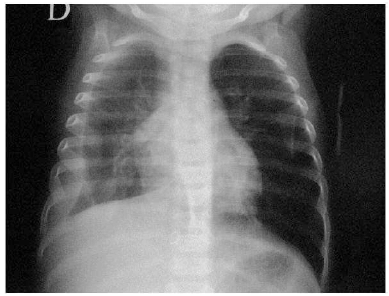

Uma criança de dois anos apresenta há três dias tosse, coriza e febre alta. Nas últimas 24 horas, passou a ficar mais prostrada e taquidispneica. Foi solicitada uma radiografia de tórax, que apresentou o seguinte resultado:

Com base no resultado do exame, deve-se proceder da seguinte forma: